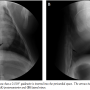

Percutaneous subxiphoid pericardial access was obtained by the use of the micropuncture set as described previously.18 Briefly, under fluoroscopic guidance (BV Pulsera; Philips Medical Systems) in lateral projection, a 21 gauge two-part trocar needle was inserted subcutaneously and advanced in the midline direction along the posterior surface of the sternum into the anterior mediastinal space. The entry site of the pericardium was targeted at the anterior heart wall approximately 2 cm cranially to the heart apex. When the tip of the needle punctured the pericardium and myocardium, self-limiting premature ventricular contractions were usually noticed with ECG monitor. The correct needle position was indicted by pulsatile motion of the needle tip. After removal of the stylet of the needle, a 0.018˝ micro guidewire from micropuncture set (5 Fr Micro Access Kit, AngioDynamics) was gently inserted through the needle cannula into the pericardial space as confirmed by the wire remaining within the cardiac silhouette during fluoroscopy in various projections (Figure 1). The needle cannula was removed and the coaxial micropuncture dilators were placed over the guidewire into the pericardial space. Through the outer dilator of the coaxial system, 5 mL of diluted contrast agent (Urografin 76%; Schering, Inc) with saline solution was injected to verify the dilator inside the pericardial space.